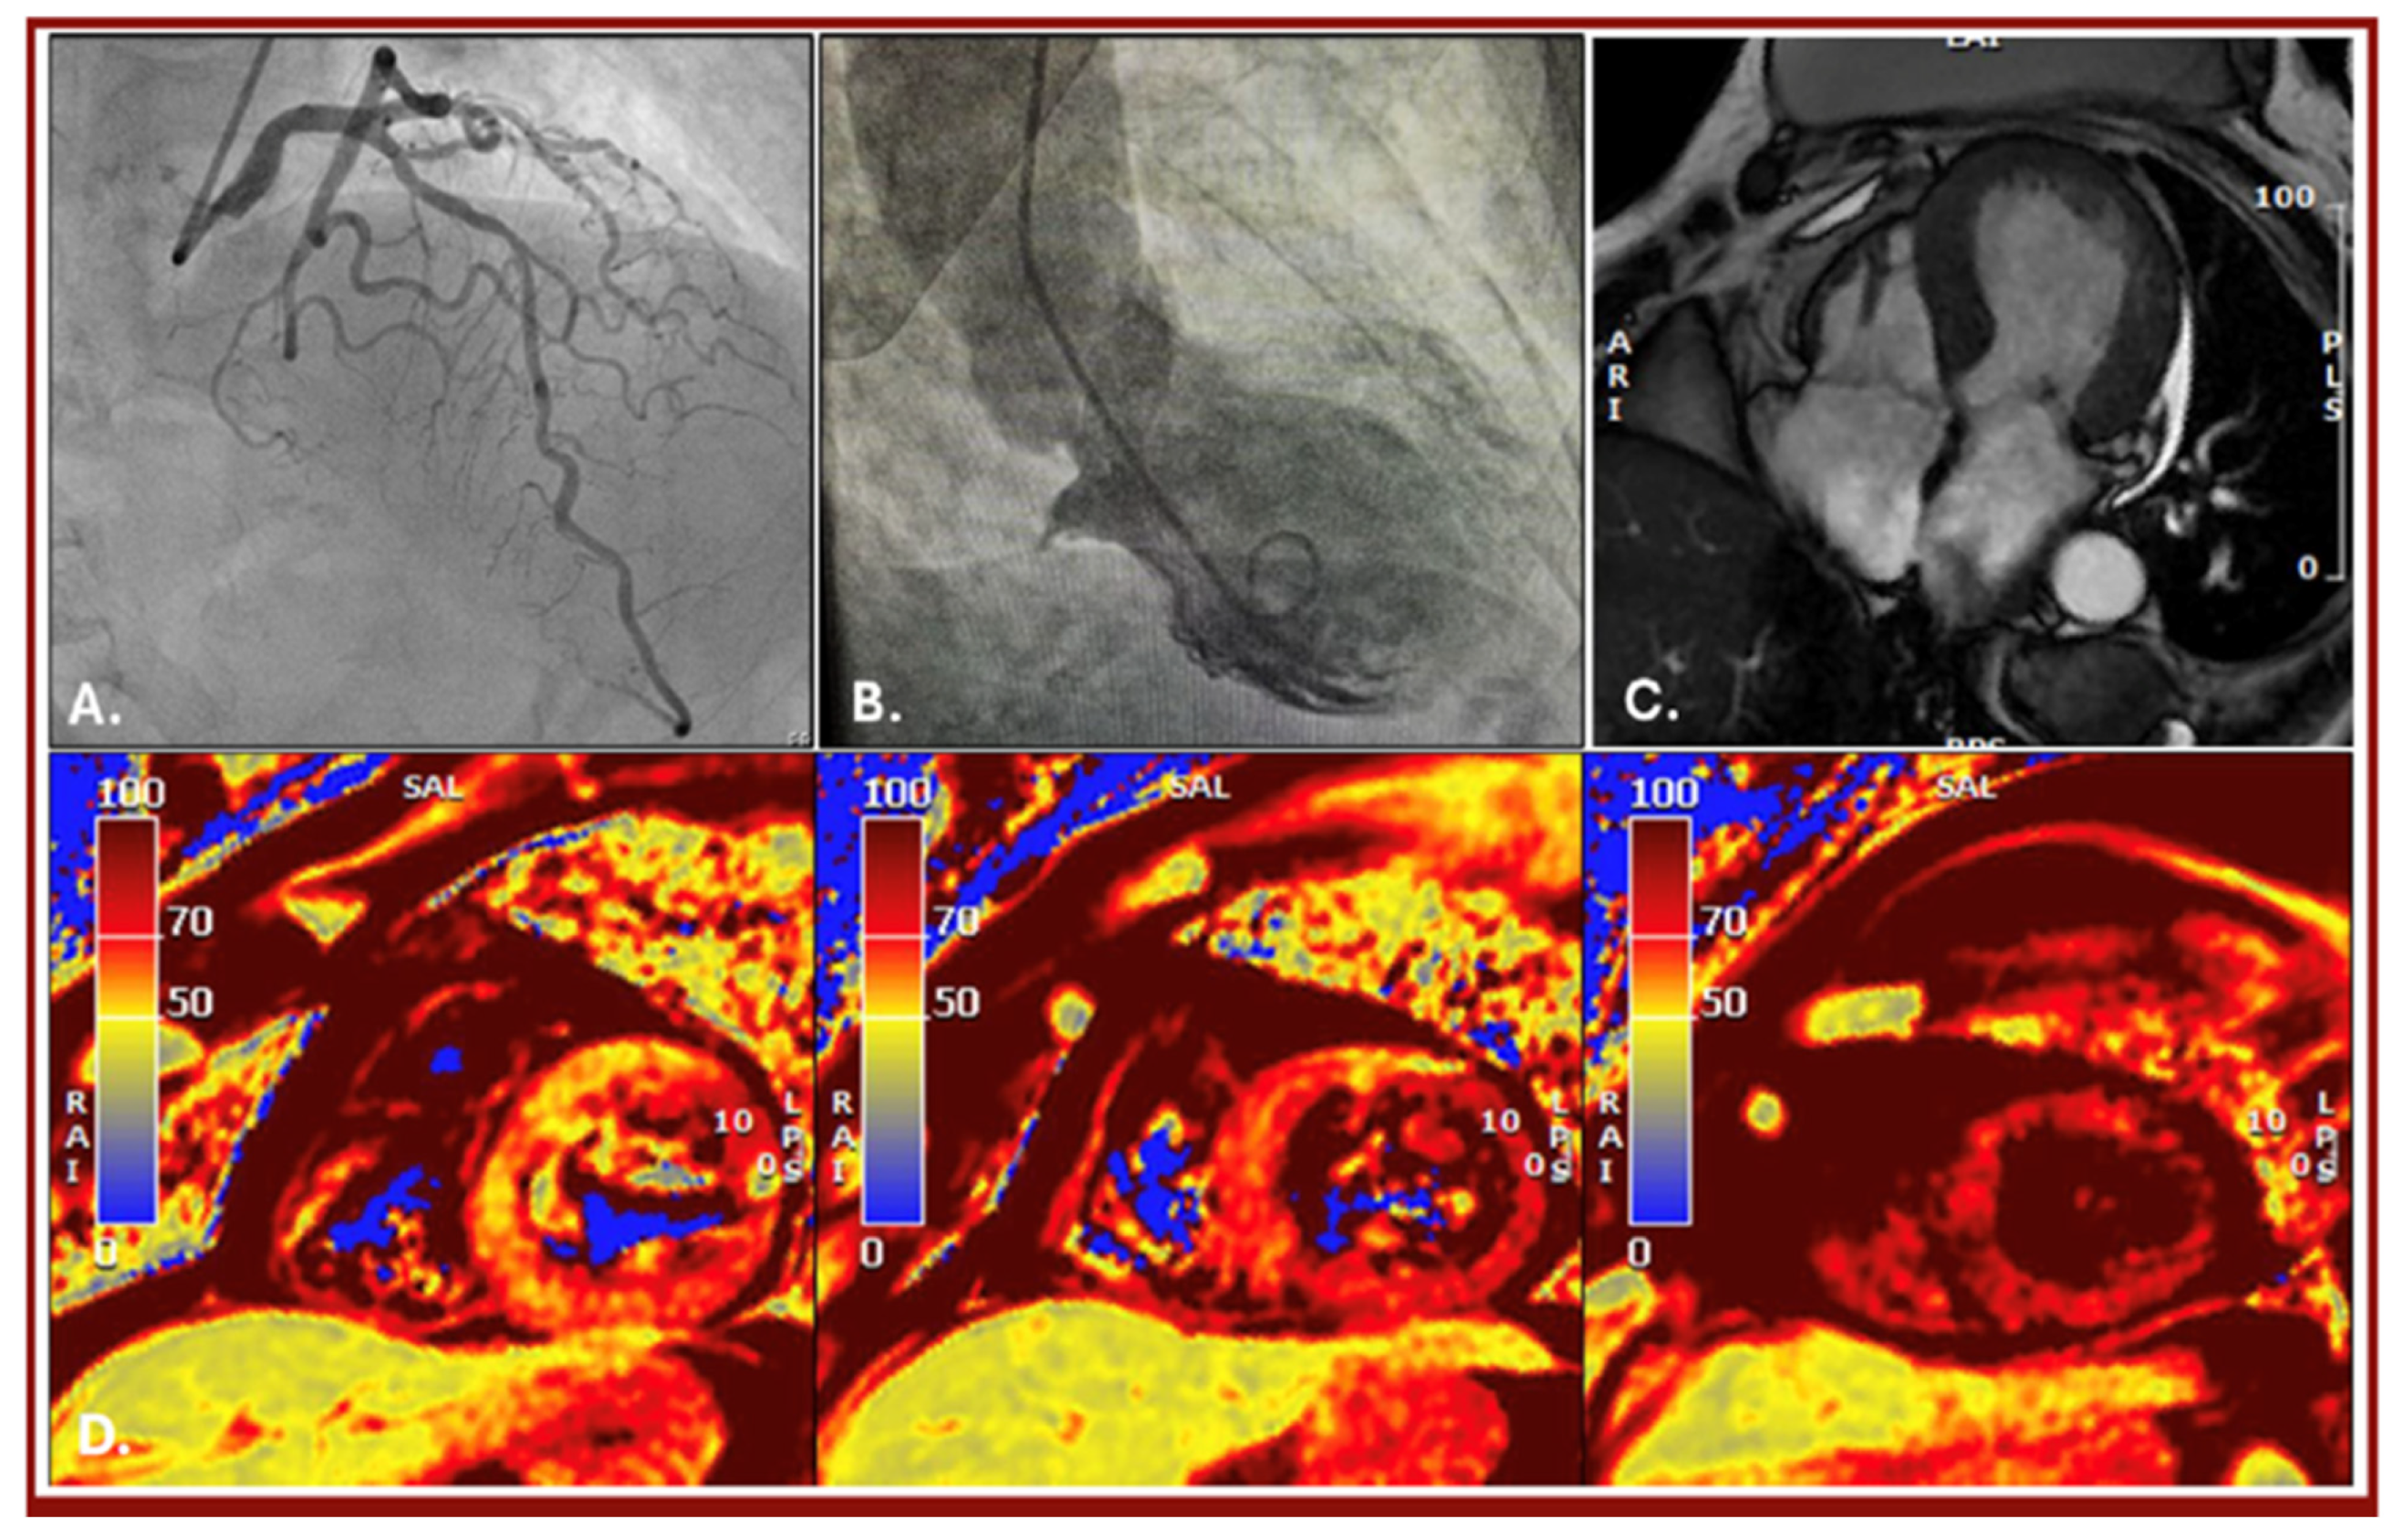

Multimodality Imaging in the Diagnosis of an Early Tako-Tsubo Syndrome Recurrence

Berloni, M.L.; Annoni, A.D.; Moltrasio, M.; Baggiano, A.; Pontone, G. Multimodality Imaging in the Diagnosis of an Early Tako-Tsubo Syndrome Recurrence. Diagnostics 2026, 16, 292. https://doi.org/10.3390/diagnostics16020292